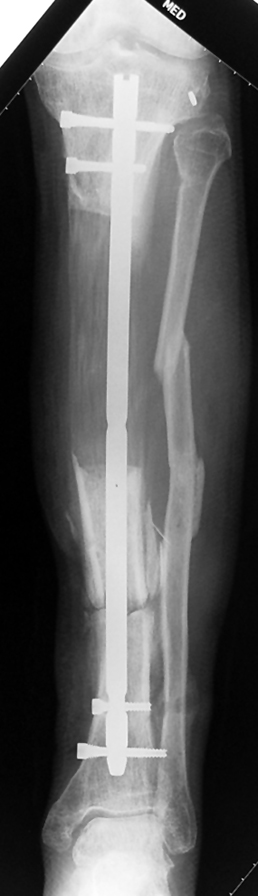

Eksternal fiksatör ile geçen süre (eksternal fiksasyon indeksi), gereken distraksiyon miktarına bağlıdır ve bu süre boyunca bazı komplikasyonlarla karşılaşılabilir. Distraksiyon dönemi sona erdikten sonra, distraksiyon süresinin iki katını aşan konsolidasyon döneminde hastalar eksternal fiksatörü zorlukla tolere edebilirler. Yeterli konsolidasyon sağlanmadan eksternal fiksatör çıkartılırsa ise kırıklar, deformite ve kısalık oluşabilir. Hastanın fiksatör ile birlikte geçirdiği sürenin azaltılması ve böylece hasta konforunun ve aktivite düzeyinin arttırılması için intramedüller çivi üzerinden uzatma yöntemi uygulanmaktadır. Bu yöntemde distraksiyon dönemi sona erdiğinde kemiğin içindeki çivi statik olarak kilitlenmekte ve eksternal fiksatör çıkartılmaktadır. Stabilizasyon intramedüller çivi tarafından sağlandıktan sonra konsolidasyon dönemi gerçekleşmektedir. Bu şekilde hem eksternal fiksatörün uzun süre kalmasından hem de erken çıkartılmasından kaynaklanan komplikasyonların önüne geçilmektedir.

Vaka 3